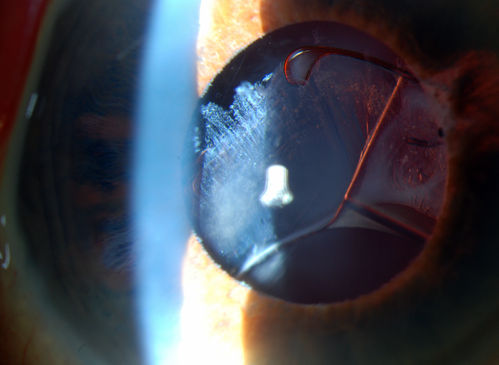

Subluxated Crystalline IOL with Pseudoexfoliation

82-year old male comes in with blurriness on the bottom half of his vision. Patient's VA was 20/25. Slit lamp examination shows subluxated crystalline lens inferiorily. Pseudoexfoliation debris superiorly at 10 o'clock with no vitreous present in the anterior chamber. Patient scheduled for surgery for CE IOL in the right eye.